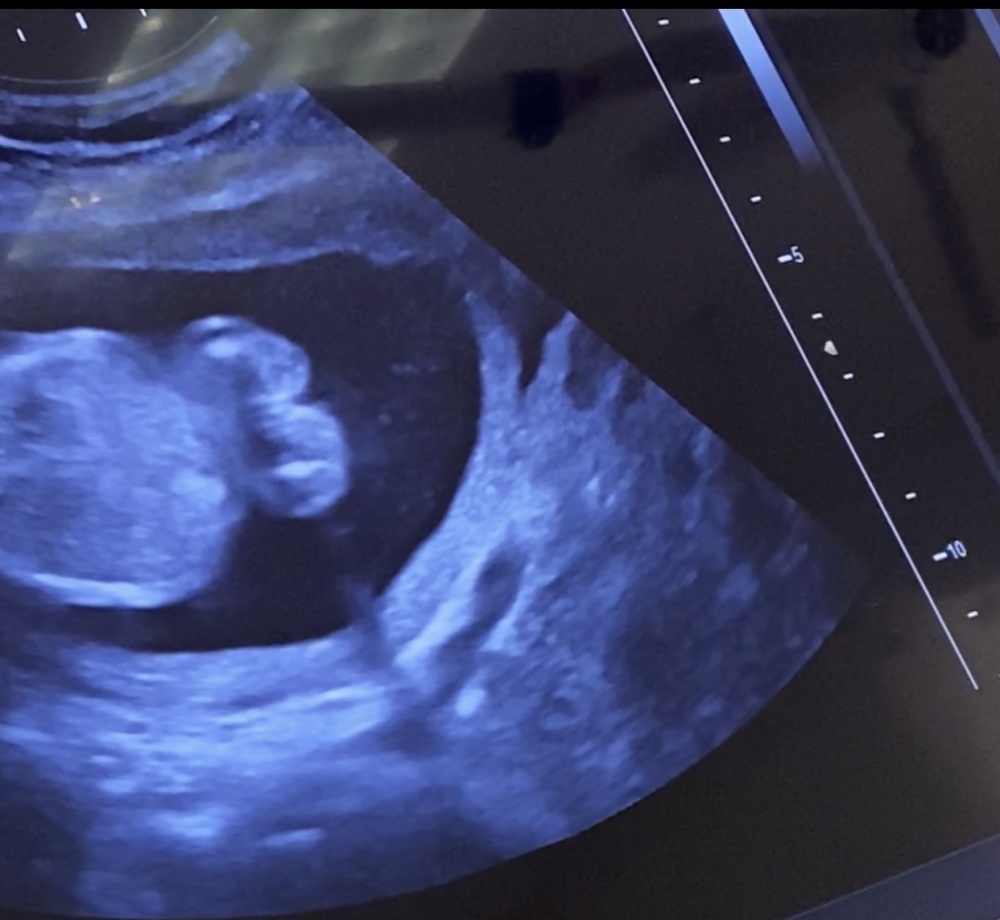

Ich hatte vor ein paar Tagen in der 15SSW (14+3) meine US Untersuchung, wo meine Ärztin auf einen Jungen tippte. Sie hatte von unten zwischen die Beinchen von dem Baby geschallt und man hatte quasi ein kleines "Dreieck" Zipfelchen erkennen können.

Aber beim ausgedruckten US Bild, was von der Seite geschallt ist, sieht es eher nach einem Mädl aus oder irre ich mich da (bezüglich der Nub Theorie) - falls man da überhaupt einem Nun drauf erkennt 😆🤔

Mir ist es letztendlich egal ob Bub oder Mädl, hab beides schon hier Zuhause 😁 Hauptsache gesund 😌 Aber neugierig ist man ja trotzdem irgendwie 😁 Vielleicht habt ihr ja eine Ahnung 😊